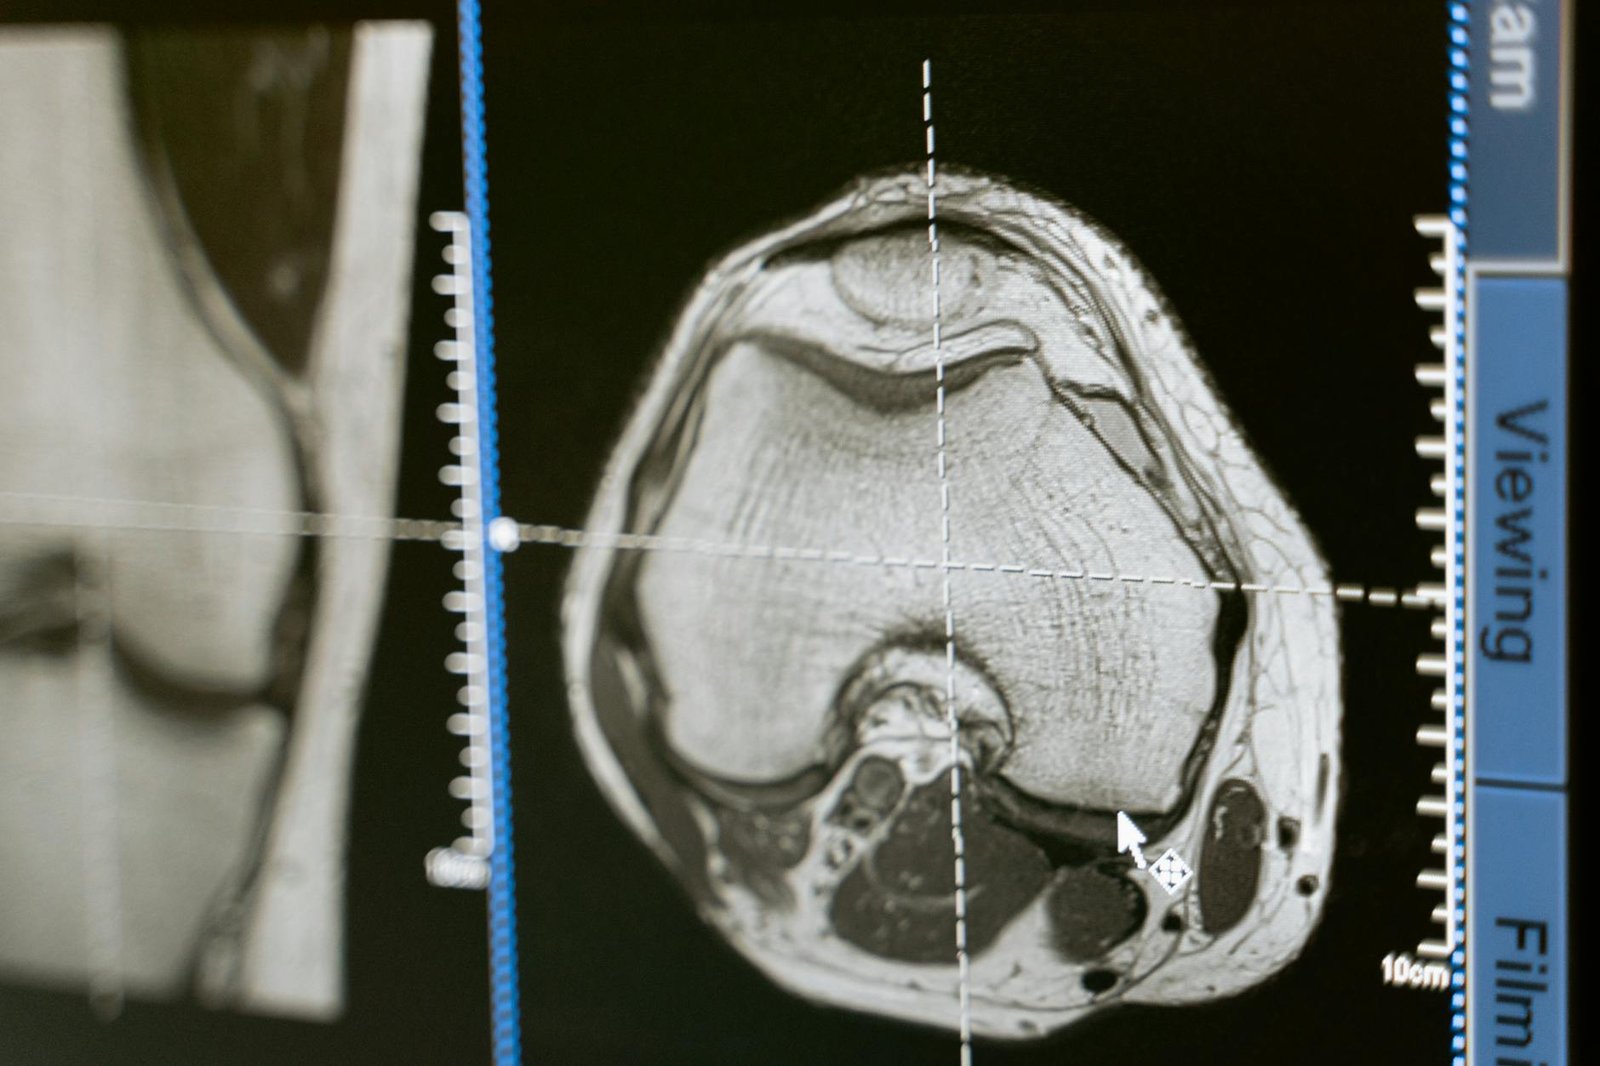

The DEXA Scan: Why It’s a Game Changer

Forget the scale. My DEXA showed I had 22 pounds of lean mass but also 18% body fat. The breakdown mattered: I had 4.5 pounds of visceral fat. That’s the metabolically active stuff linked to heart disease and diabetes. The technician said my goal was to get that under 2.5 pounds. Cost? It’s $175 if you book it standalone, but it’s included in their full audit package.